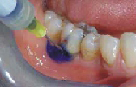

FotoSan 360

Přístroj na principu světlem aktivovaná desinfekce neboli fotodynamická antimikrobiální chemoterapie. Přístroj s okamžitým účinkem ničí veškeré mikroorganismy bez jakýchkoli vedlejších účinků. Jedná se o bezbolestné ošetření, které nevyžaduje anestezii, nemá vedlejší účinky a ničí 99% bakterií. Používá se především v parodontologii a implantologii při léčbě zánětů v okolí zubů a implantátů (dezinfekce tzv. chobotů), záchovné stomatologii (ošetření kazů) i endodoncii (dezinfekce kanálků zubu).